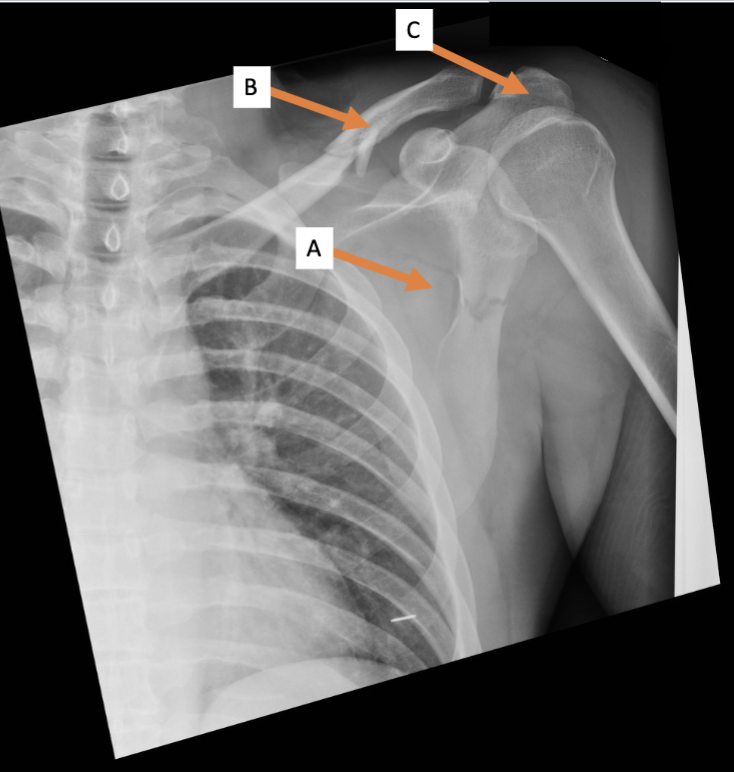

A. Identify structure

Transverse foramen; Vertebral a.

B. Identify structure; What goes through this feature?

Transverse process

C. Identify structure

Scapula

A. Identify the bone

Clavicle

B. Identify the bone

Acromion process

C. Identify the structure